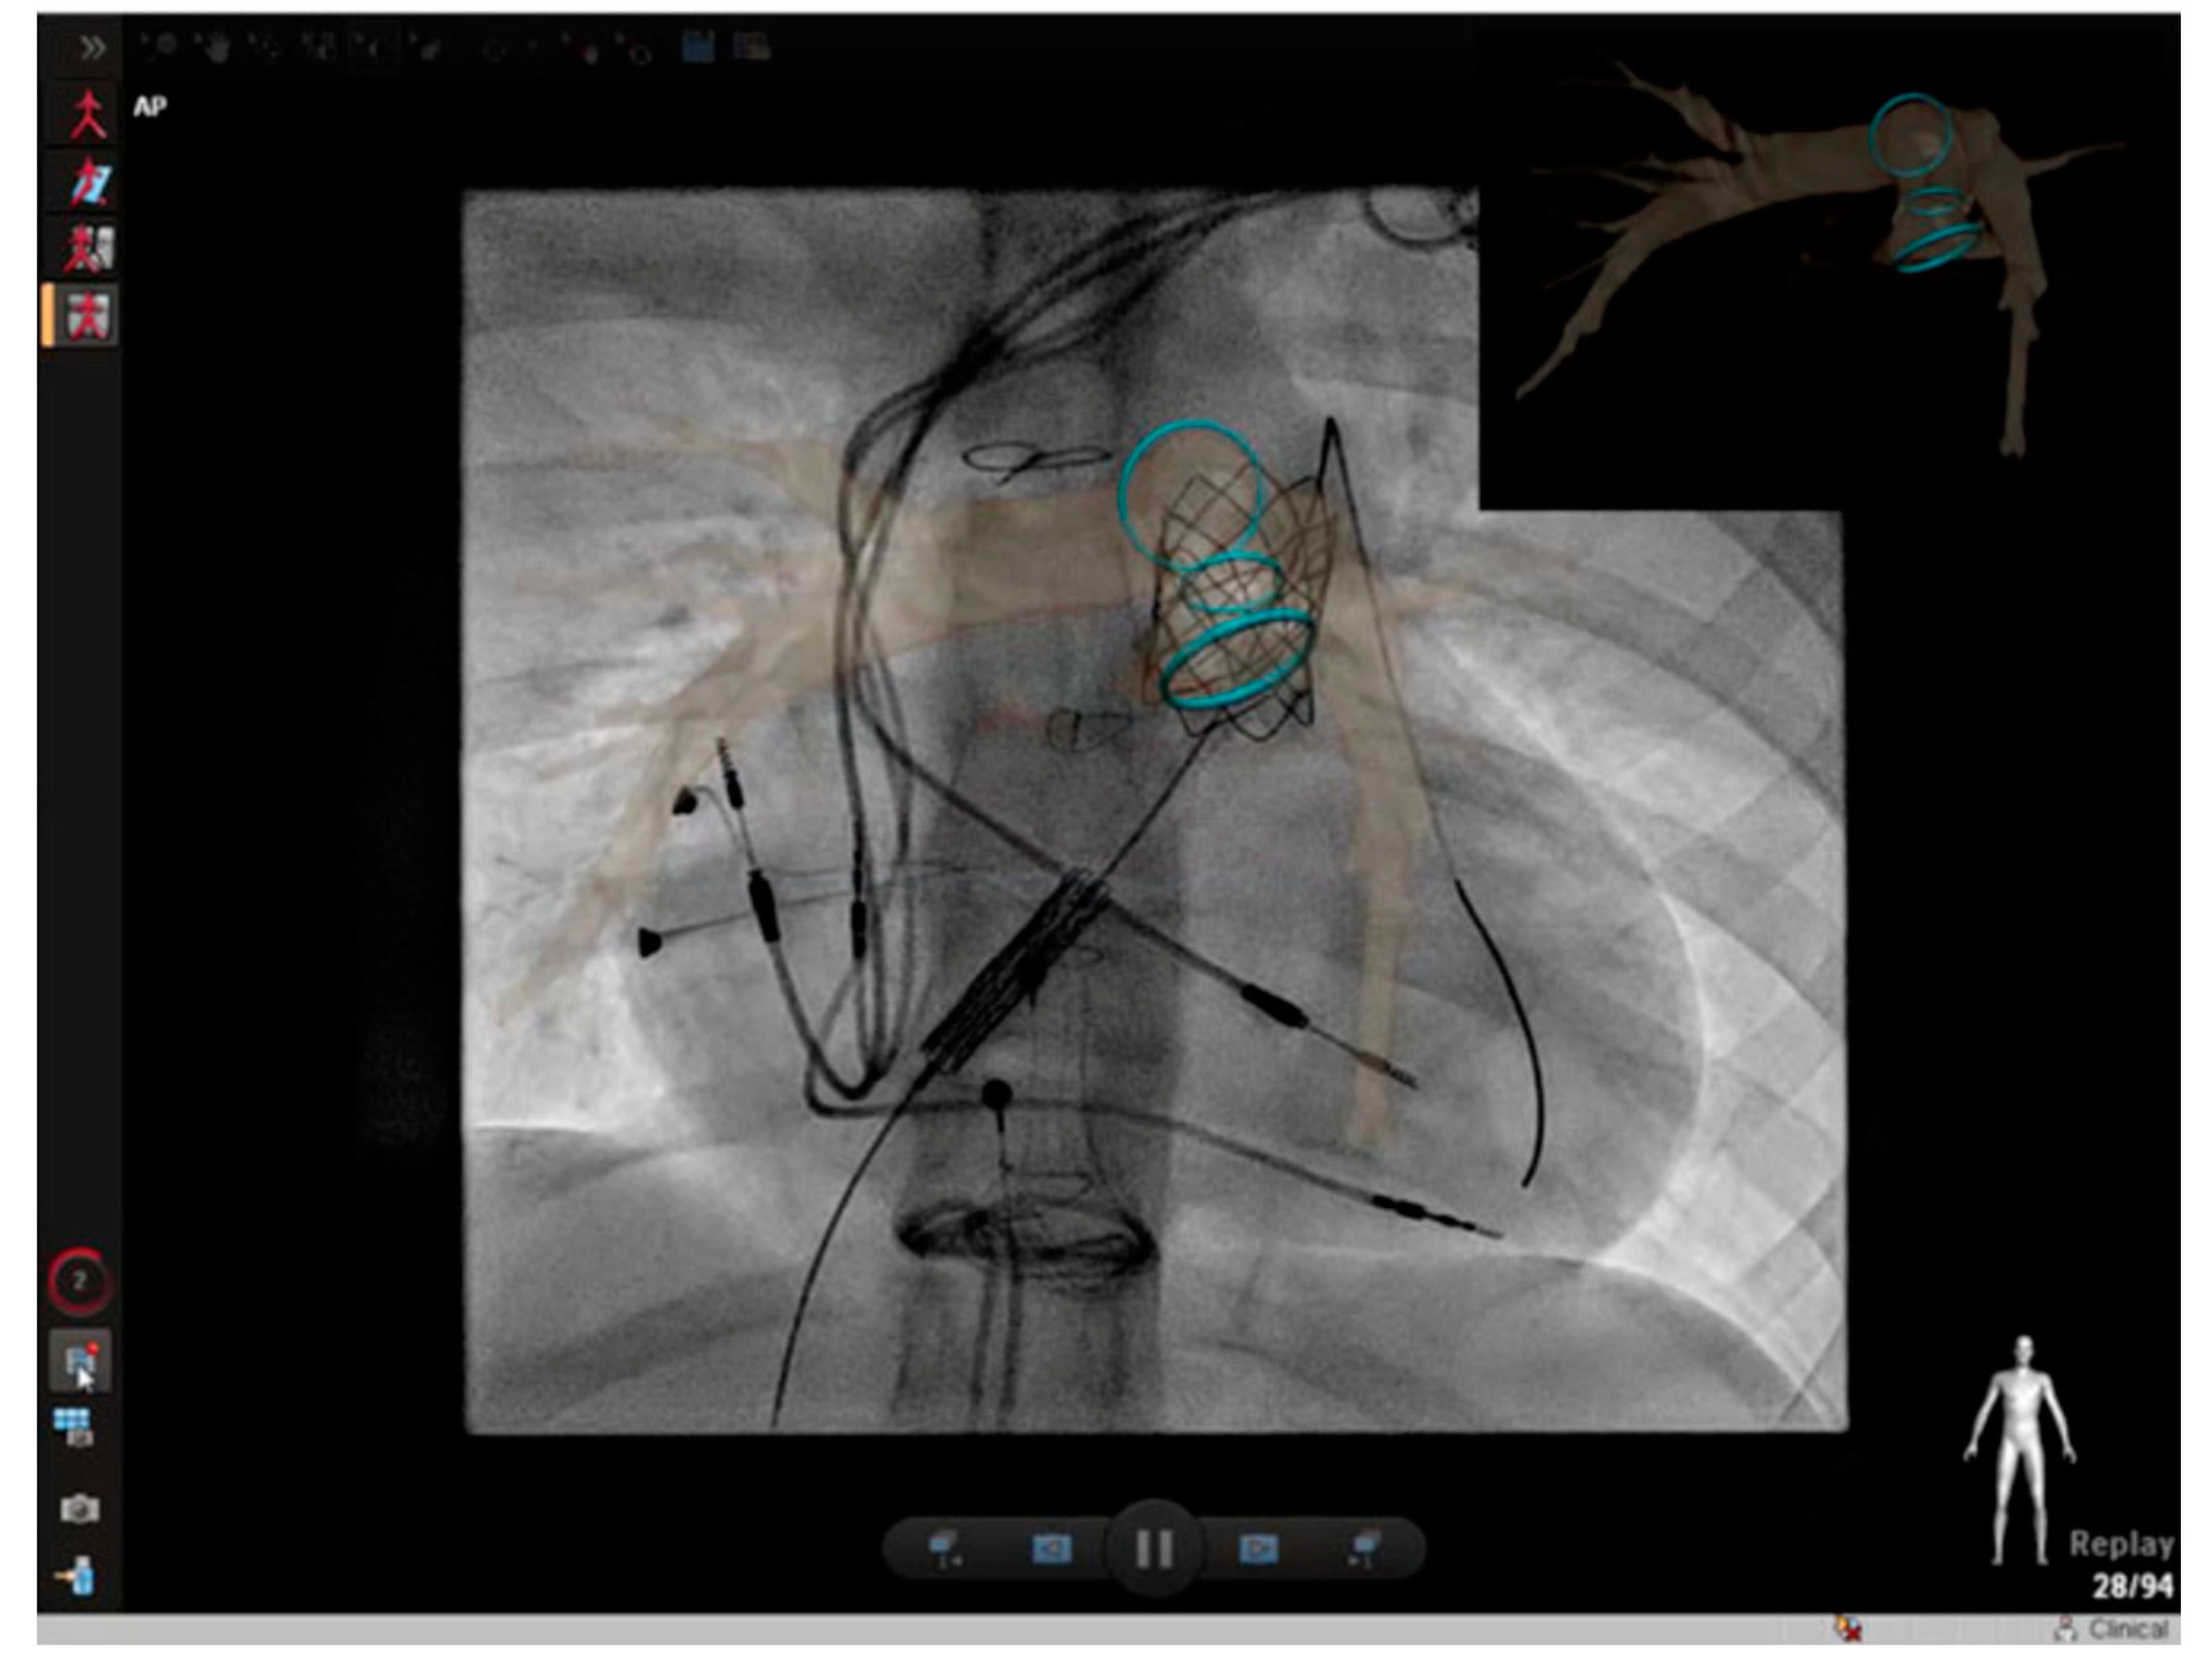

2.4. Cross-Sectional Overlay Fusion in the Catheterization Lab

2.5. Coronary Artery Assessment in CHD